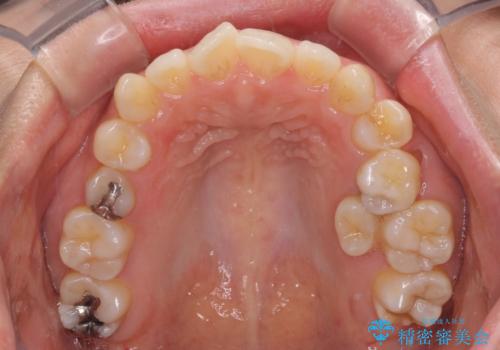

左上奥歯には乳歯が残存しており、後続永久歯は舌側に転位していました。

乳歯を抜歯し、舌側の永久歯を引っ張り出すこととしましたが、希望のインビザラインでは移動量が大きすぎて対応できない可能性があったため、ワイヤー装置にて改善することとしました。

ワイヤー装置にてある程度歯列が改善されたところで、上下をインビザラインにて矯正治療を行うこととしました。